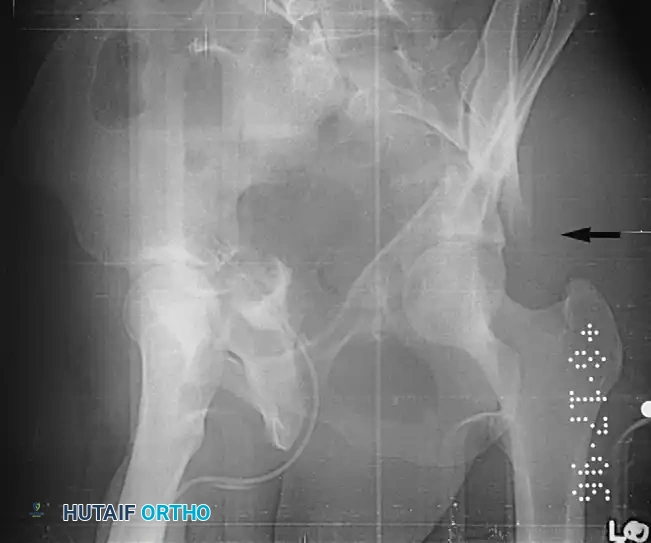

- Both-Column Fractures: The most complex pattern. All articular segments are detached from the intact posterior ilium (which remains attached to the sacrum).

Clinical Pearl: The Spur Sign

In a both-column fracture, the intact portion of the ilium (attached to the sacroiliac joint) projects laterally relative to the medially displaced, fractured acetabular columns. On an obturator oblique radiograph, this intact bone appears as a sharp spike, known as the "Spur Sign." Its presence is pathognomonic for a both-column fracture.